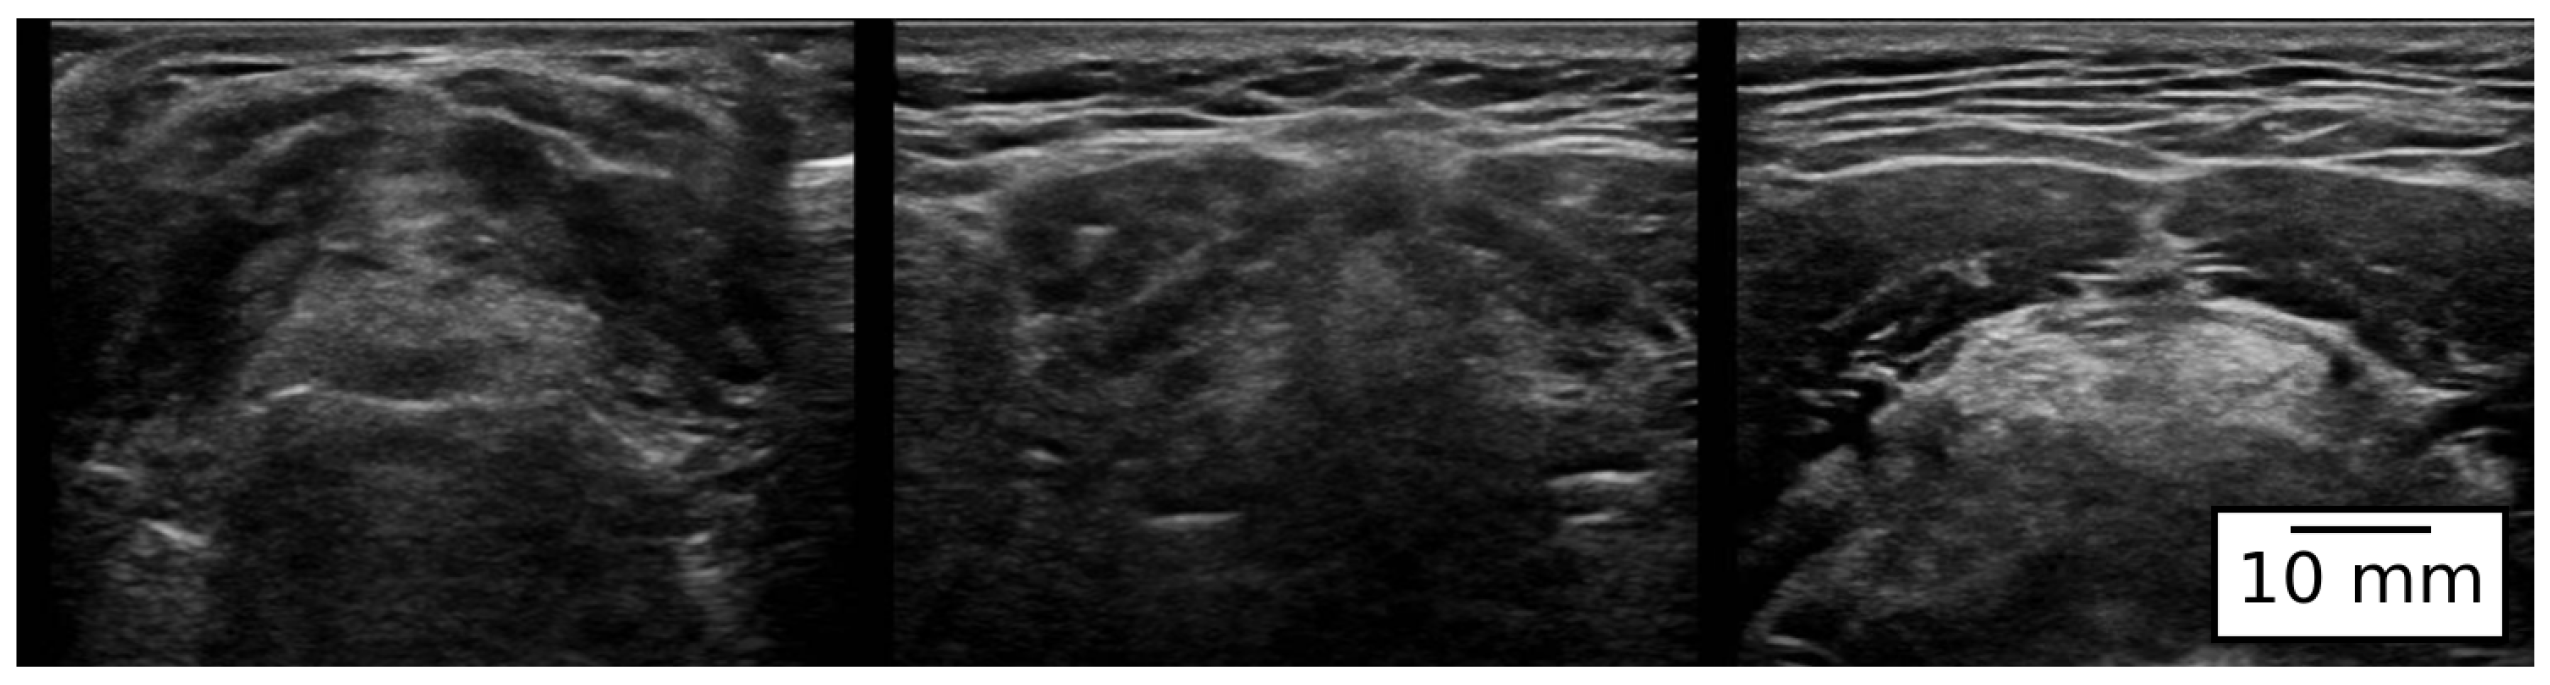

This study was conducted on 300 patients planned for surgery under total anesthesia at the Affiliated Hospital of Qingdao University in China. Each participant provided written informed consent. All patients participating in this study consented to the inclusion of their images, clinical data, and other related information for publication. This study adheres to all applicable regulations, and patients were included according to the following four criteria: (1) the patient is over 18 years old; (2) patients undergoing planned surgery under general anesthesia; (3) patients categorized as having an ASA (American Society of Anesthesiologists) clinical status of I–III; (4) patients who voluntarily signed the informed consent. Acquisition of Patients’ Laryngeal Ultrasound images (Figure 1). To maintain the integrity of anatomical structures, the original laryngeal ultrasound images were preserved in their native aspect ratio during preprocessing. The raw output of the ultrasound device generated images with a resolution proportional to 549 × 364 pixels. Therefore, we adopted this non-standard size to avoid distortion that would occur if the images were resized to common square dimensions (e.g., 224 × 224). This choice ensured that spatial relationships among airway structures, such as the trachea and epiglottis, were retained without stretching or compression, while also balancing feature preservation with computational efficiency. In clinical ultrasound practice, the imaging depth (echo depth) may vary across subjects because of differences in neck circumference and soft-tissue thickness; consequently, minor depth adjustments are sometimes required to ensure complete visualization of the laryngeal region. In this study, all images were retained at their native resolution and aspect ratio to avoid geometric distortion. To alleviate residual scale variability associated with depth changes, we employed a data augmentation pipeline that included mild scaling transformations. In this study, the ground-truth labels for airway difficulty were obtained from intraoperative video laryngoscopic assessments, following the Cormack–Lehane (C-L) classification: Grade I, full view of the glottis; Grade IIa, posterior glottis visible; Grade IIb, no glottic opening with only arytenoids/posterior epiglottis visible; Grade III, epiglottis only; Grade IV, neither epiglottis nor glottic structures visible. The grading was independently performed by two anesthesiologists with ≥5 years of clinical experience. In cases of disagreement, a consensus was reached through discussion. To assess inter-observer agreement prior to consensus, we calculated Cohen’s Kappa, which showed a substantial level of agreement ( κ = 0.81 ). To ensure consistency, all evaluations were conducted at the best obtainable view in the sniffing position, permitting external laryngeal pressure (BURP) if needed. According to clinical convention, we defined C-L Grades I–II as the non-difficult (simple) group and Grades III–IV as the difficult group. This labeling strategy ensured that the dataset reflects intraoperative ground-truth outcomes rather than purely visual interpretation of ultrasound images. Among the 300 enrolled subjects, ultrasound image acquisition was performed using a standardized protocol, where one echo image was captured per subject at a fixed view/angle. Three images with extremely poor quality (e.g., severe artifacts or inadequate visualization of laryngeal structures) were excluded during quality control, resulting in a final dataset of 297 images. The class-wise distribution was as follows: Class I ( n = 121 ), Class II ( n = 68 ), Class III ( n = 55 ), and Class IV ( n = 53 ). Accordingly, the simple-airway group (Classes 1–2) contained 189 images, whereas the difficult-airway group (Classes 3–4) contained 108 images.

Figure 1. Laryngeal ultrasound image of surgical patients.